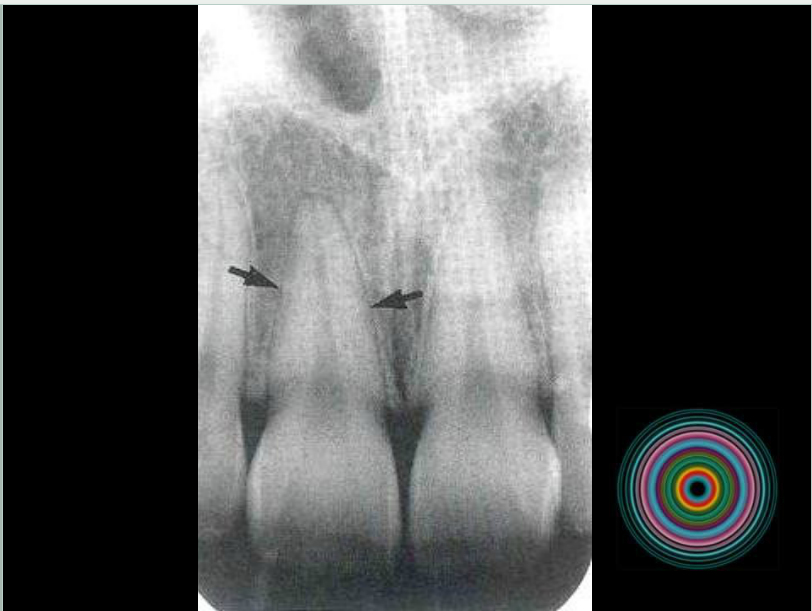

口腔頜面外科 影像技術(shù)